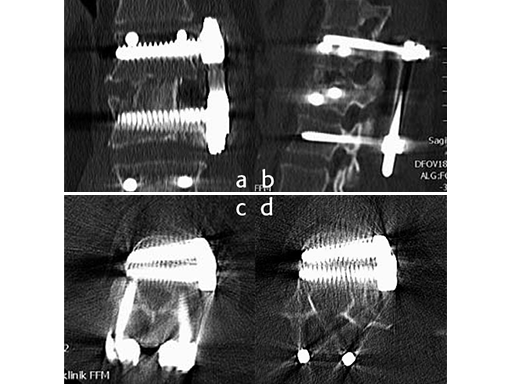

Using the USS Fracture MIS system for the initial stabilization allowed for a minimally invasive approach with intraoperative active reduction of the spinal fracture. The unique design of the fracture clamp allowed for independent correction of the sagittal alignment (Fig a) as well as height readjustment (Fig b).

For this patient, independent lordosis correction, height readjustment, and spinal stabilization were the primary goal of surgery. As percutaneous toploading pedicle screw systems cannot provide independent correction of the flexion-compression deformity, the fracture clamps and Schanz screws of the USS Fracture MIS system were used to overcome this disadvantage.

Follow up CT Scans (AP, lateral and coronal) after the second surgery.